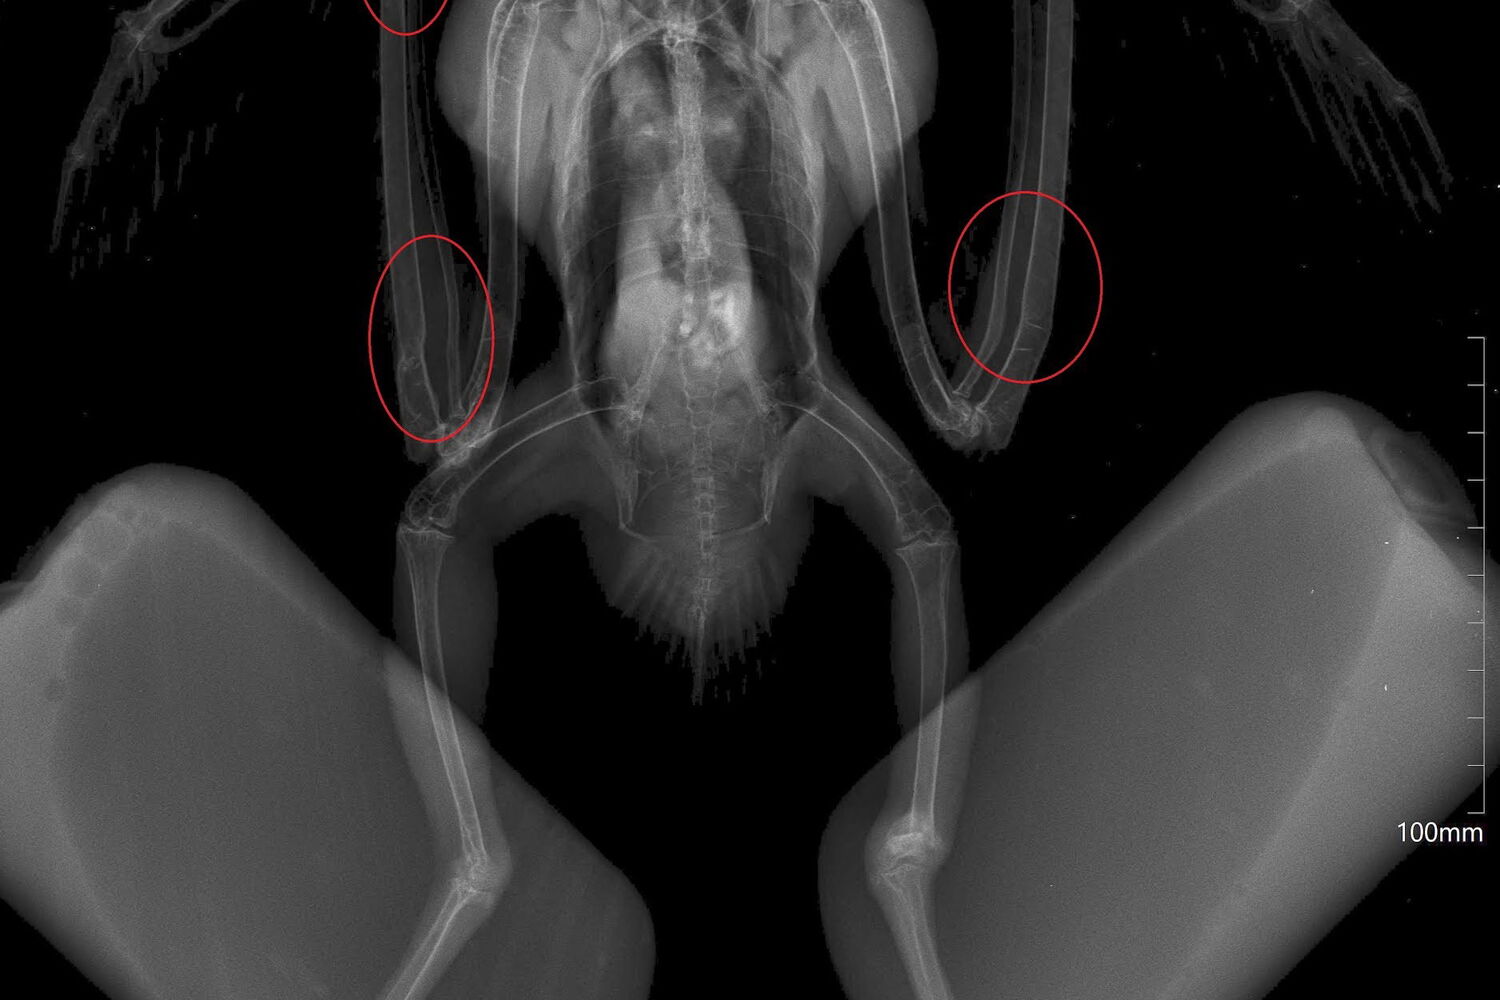

Um milhafre-preto ainda juvenil deu entrada no RIAS - Centro de Recuperação e Investigação de Animais Selvagens, em Olhão, depois de ter sido mantido ilegalmente em cativeiro. Tinha várias deformidades ósseas nas asas e nas patas devido a alimentação inadequada.

“O raio-x mostrou graves deformidades nos ossos, um sintoma compatível com osteodistrofia nutricional, uma patologia frequente em animais com alimentação inadequada durante o crescimento”, refere o RIAS, revelando ainda que “não vai ser possível corrigir estas alterações ósseas.” Ainda assim, a ave, que terá nascido no início deste ano e está no centro desde o final de julho, consegue voar, mas apresenta outro problema: alterações comportamentais que afetam a alimentação.